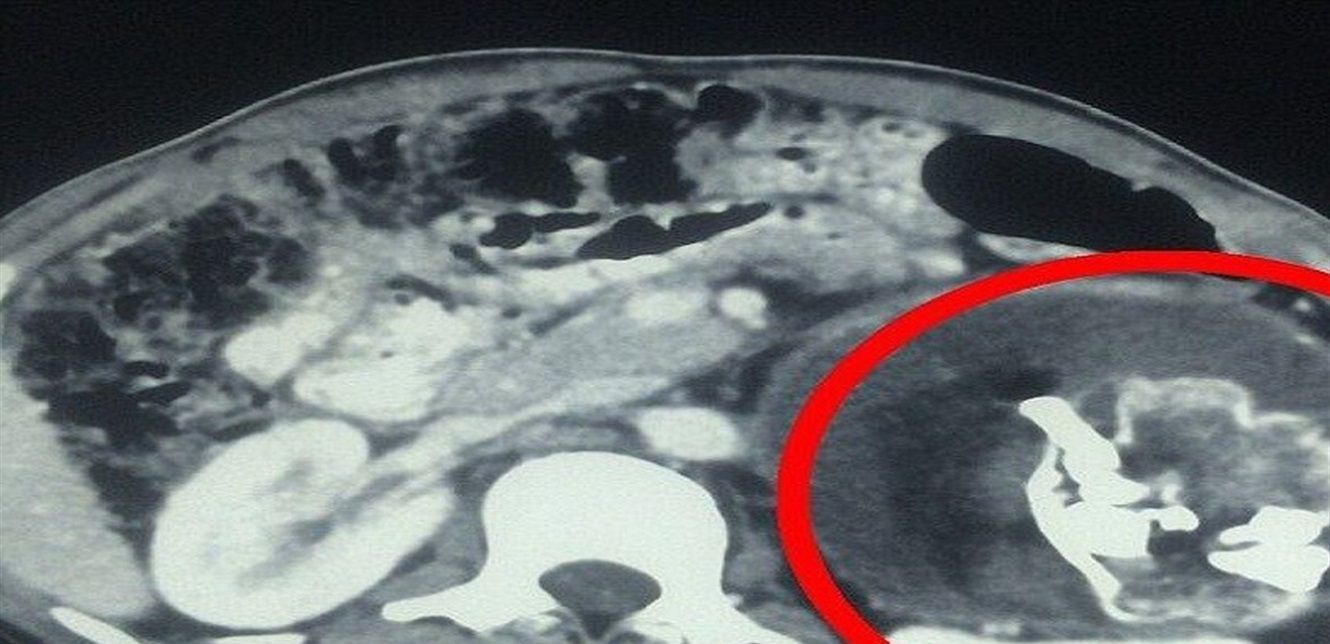

وفقا لما نشرته صحيفة Need To Know فإن مستشفى كابول استقبل طفلا يعاني من انتفاخ في البطن. واشتبه الأطباء أولا بإصابته بورم "ويلمز" (ورم كلوي) يظهر أحيانا لدى حديثي الولادة. لكن الفحص بالأشعة كشف وجود تكوين في تجويف البطن يضم أنسجة رخوة، من الدهون والسوائل والبنية العظمية".

وتمكن الأطباء من التعرف على عظام وجه متكونة، وعمود فقري، وأضلاع في الصورة.